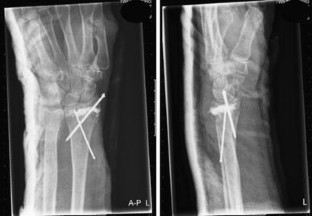

Fig. 1

Distal radius fractures are one of the most common fractures in the elderly females. In this article, we report a case of a distal radius fracture type AO-A3 with dorsal instability, in an older woman with manifest osteoporosis, treated with minimally invasive Cortoss® composite and FFS-wires®. A 63-year-old woman sustained an unstable distal radial fracture of her left wrist after falling from a kitchen step. She underwent an open reduction of the fracture and fixation with two crossed-fixation pins and Cortoss® composite. Post-operative plaster cast immobilization was given for 2 weeks, after which the plaster cast and the fixation pins were removed. At 4 weeks follow-up, she had a good functional result of her left wrist, after 11 months there was a complete return of grip strength with also, except for the palmar flexion, a full return of function. We report here the first case of a successful surgical treatment with Cortoss® composite of an AO-A3 type distal radius fracture.